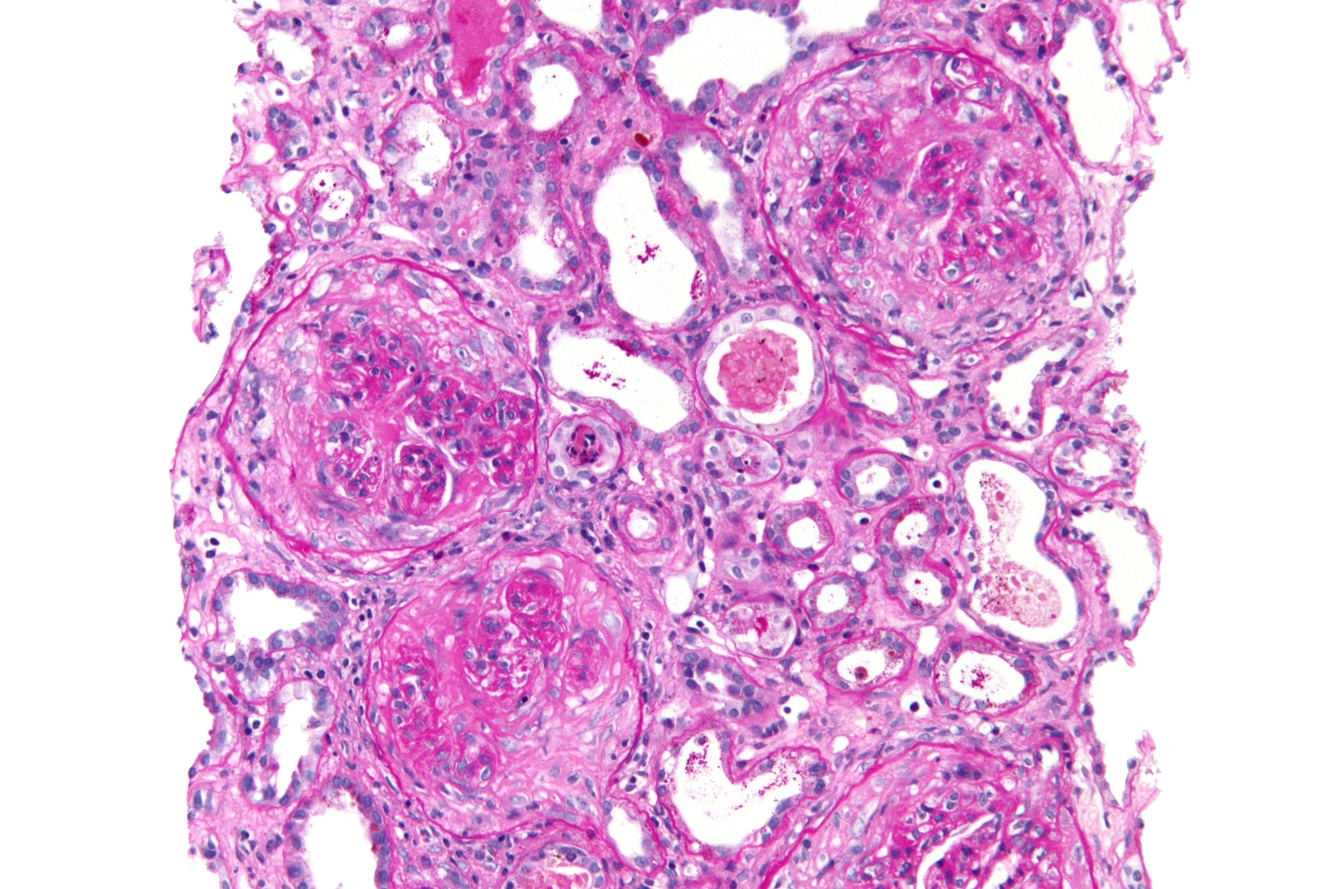

Goodpasture’s disease

anti GBM disease

can also be seen in small vessel (ANCA) vasculitis

Histology: crescentic glomerulonephritis with linear IgG and C’ on basement mmb

Ab against proteinase 3 (cANCA) or myeloperoxidase (pANCA)

limited to ffecting glomerularand alveolar caps (not small arteries)

linearIgG can be seen in antiGBM, fibrillary glomerulonephropathy, and diabetic glomerulosclerosis